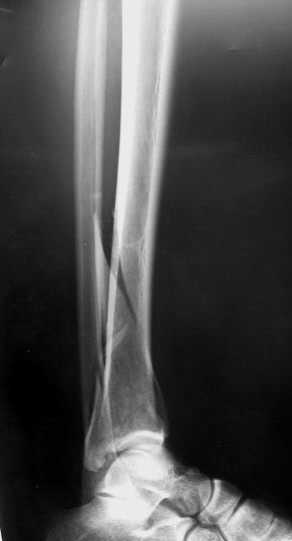

Пример - довольно похожий перелом, оперированный в первые 8 часов после аварии у 40-летнего больного, страдающего тяжёлым сахарным диабетом 1 типа.

По поводу обсуждаемого случая - 6-недельная фиксация такого перелома значительно увеличила шансы на артроз голеностопного сустава. Дальнейшая фиксация в гипсе практически сравняет эти шансы со 100%.

1- открытая редукция с наложением аппарата Илизарова и разработка движений в суставе.

2.- снятие гипса, разработка сустава, И коррегирующая супрамаллеолярная остеотомия с фиксацией в аппарате Идизарова через полгода.